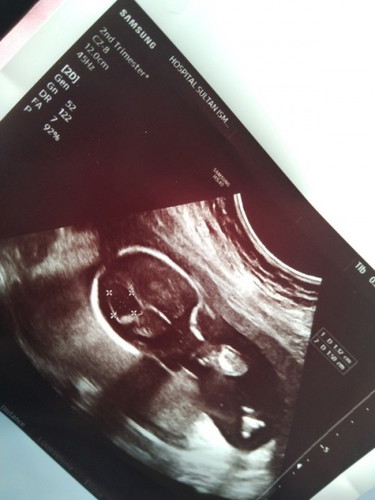

Kepala baby dalam kandungan bengkak..

Assalamualaikum, Saya baru lepas scan dgn pakar kt HSI Pakar kata kepala baby ada bengkak. Skrg saya 22w, suspect ada cyst kt bahagian dlm kepala baby. Ada tips ke utk kurangkan atau hilangkan cyst dalam kepala baby... Mohon doa semua semoga anak dalam kandungan sy baik2 saja.. Rasa rasa sedih dan risau bila tahu keadaan kandungan sy... Nnti 22/6 ni kne refer yg pakar HSA... Harap tiada yg serius... Doakan yg terbaik utk baby sy... Terima kasih sgt2. #ingintahu #pleasehelp #firstbaby

Waalaikumsalam sis, boleh saya tahu cyst di bahagian kepala baby tu ada di setiap bahagian ke atau sebelah sahaja? kalau sebelah just perlukn pemantauan pakar sahaja sbb nnti lama2 dia akan hilang, itu sama seperti situasi saya masa 22 week pregnant, saya kena refer ke pakar o&g dan jumpa specialist dekat hospital mahkota melaka sepanjang pemantauan tu dr akan scan dan tgk ukuran saiz cyst membesar atau tak untill 28-32 week mcm tu.. alhamdulillah dua kali follow up dekat o&g dan specialist after 26week cyst tu dah xde.. menurut pakar ini xde kaitan dgn cara pemakanan atau apa, itu merupakan sebahagian dari pertumbuhan otak baby dan juga ujian.. pengalaman saya apa yg saya lakukan first saya setkn mind positif yang anak saya akan sihat sempurna sama mcm baby normal yg lain.. bykkn membaca surah yassin ayat ke 82 dekat kun tu angkat tangan munajat dan merayu pada allah agar diberi kesembuhan dan dijauhi daripada sebarang kemudaratan pada ibu dan baby selepas hajat tu tutup dgn fayakun... bykkn berzikir ya hafiz ya muhaimin sambil usap2 perut 7x melawan arah jam.. bykkn mengaji dan solat hajat sepanjang preggy mmg saya dan suami xkan tinggal solat hajat agar allah lindungi saya kandungan dan suami.. otherwise saya bykkn makanan berkhasiat buah2an.. kurangkn pengambilan gula,bahan perisa,makanan segera ambil supplement neurogain...semoga sis dan baby sihat selamat hingga bersalin nanti saya doakan ya.. ameen..

Baca lagiWassalam. Intracranial cyst ni agak common. Masa mengandung, selalunya kita tak buat apa² intervention lagi. Then after baby keluar nanti, kita akan monitor baby secara berkala untuk tgok size cyst tu samaada makin membesar atau tak through MRI. InsyaAllah baby sihat² sahaja 😊